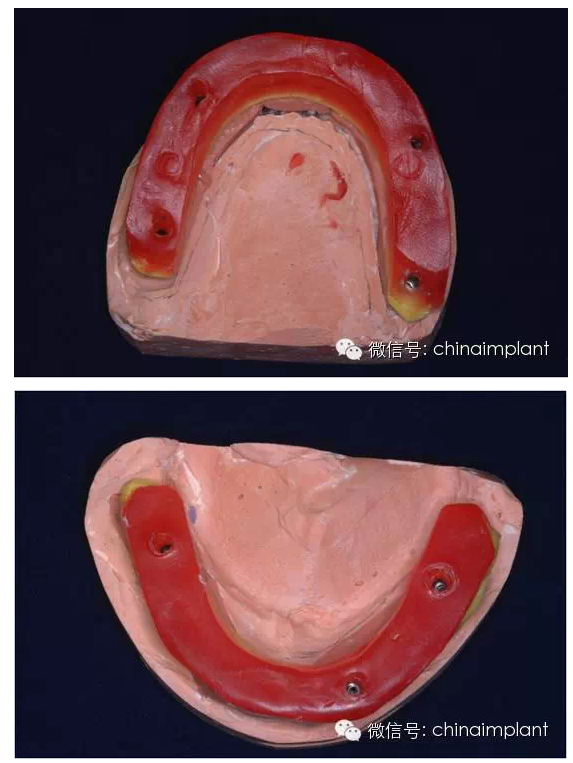

之前針對(duì)全口無(wú)牙進(jìn)行種植修復(fù)的案例中,因?yàn)轭M骨的原因,后期使用橋冠修復(fù)時(shí),一般是3部分(兩側(cè),磨牙,前牙),最近的案例中修復(fù)是一般都是做一體式的橋冠,現(xiàn)在從臨床的修復(fù)案例來(lái)看,沒有什么問(wèn)題。

之前的時(shí)候,使用圓錐形基臺(tái),但是附著的力量容易分散。(最近由于費(fèi)用的問(wèn)題多使用UCLA形態(tài)的基臺(tái))

此案例為術(shù)后兩周戴臨時(shí)牙。過(guò)去因?yàn)閾?dān)心感染的問(wèn)題,一個(gè)月以內(nèi)帶臨時(shí)牙也叫做即刻負(fù)重或者早期負(fù)重。(現(xiàn)在當(dāng)天戴臨時(shí)牙(即刻復(fù)重)的情況也非常常見).

本案例已經(jīng)將近10年了(2005年12月),但是修復(fù)效果個(gè)人認(rèn)為很不錯(cuò),所以拿出來(lái)和大家分享。